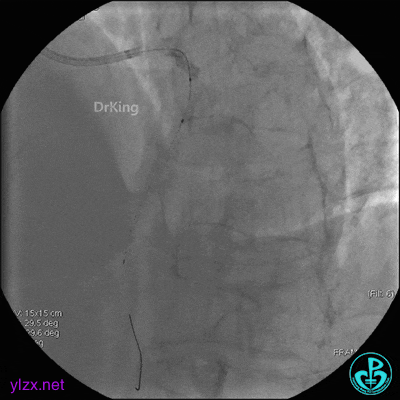

EBU指引导管到位,导丝通过闭塞段到达前降支远端,经指引导管冠脉内推注替罗非班6ml,前降支恢复3级血流,闭塞段局部残余狭窄严重,2.0×15mm球囊扩张前降支近端闭塞处后再次冠脉内推注替罗非班8ml。下台继续治疗。